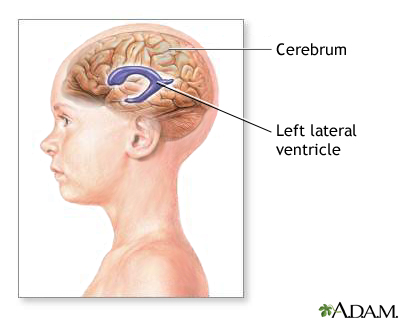

Ventriculoperitoneal shunting is surgery to treat excess cerebrospinal fluid (CSF) in the cavities (ventricles) of the brain (hydrocephalus).

This procedure is done in the operating room under general anesthesia. It takes about 1 1/2 hours. A thin tube (catheter) is passed from the cavities of the head to the abdomen to drain the excess CSF. A pressure valve and an anti-siphon device ensure that just the right amount of fluid is drained.

This surgery is done when there is too much CSF in the brain and spinal cord. This is called hydrocephalus. It causes higher than normal pressure on the brain. It can cause brain damage.

Children may be born with hydrocephalus. It can occur with other birth defects of the spinal column or brain. Hydrocephalus can also occur in older adults.